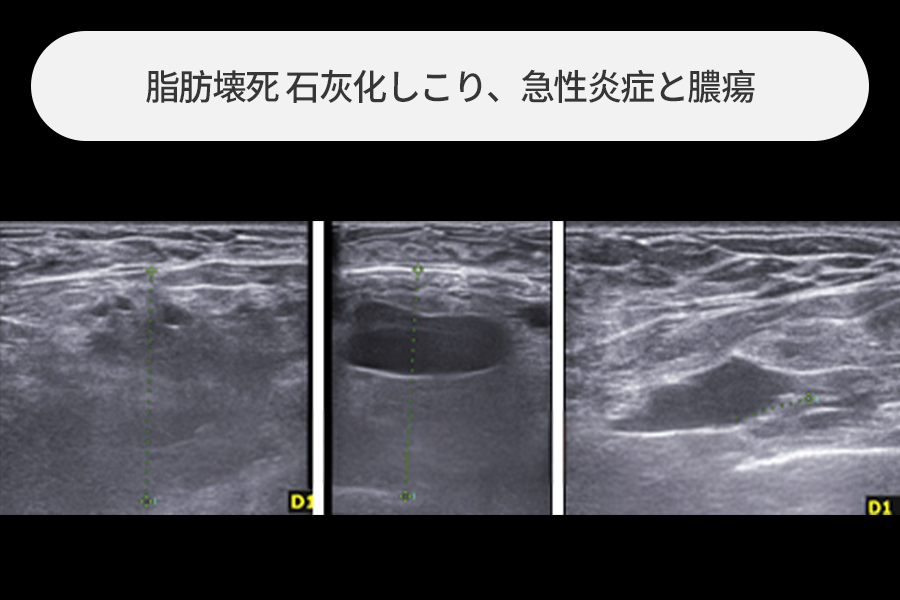

急性炎症で膿が皮膚を突き破って出た場合

胸への脂肪注入後に生じた急性炎症で膿が皮膚を突き破って外へ流れ出た状態でした。

炎症の始まりとなった脂肪壊死のしこりと血腫、損傷組織を除去し、急性炎症治療を行いました。

4~5cmの大きさの脂肪注入のしこり除去

胸への脂肪注入後に触れるしこりがあり来院された方で、

4~5cmサイズの大きな石灰化したしこりが観察されました。

サイズの大きい脂肪注入のしこりは急性炎症発生時の危険度が高いため、最大限早い除去が必要です。

超音波誘導下で正常組織を保存しながらしこりだけを安全に除去しました。

乳房内にいっぱいに溜まった膿瘍の除去

胸への脂肪注入後に急性炎症がひどく生じた方で、乳房内部に大きな膿瘍(膿の袋)が形成された状態でした。

このような場合は通常の脂肪注入副作用治療に比べて切開が大きくなり、

1~2週間程度ドレーン(排液管)の留置が必要になることがあります。